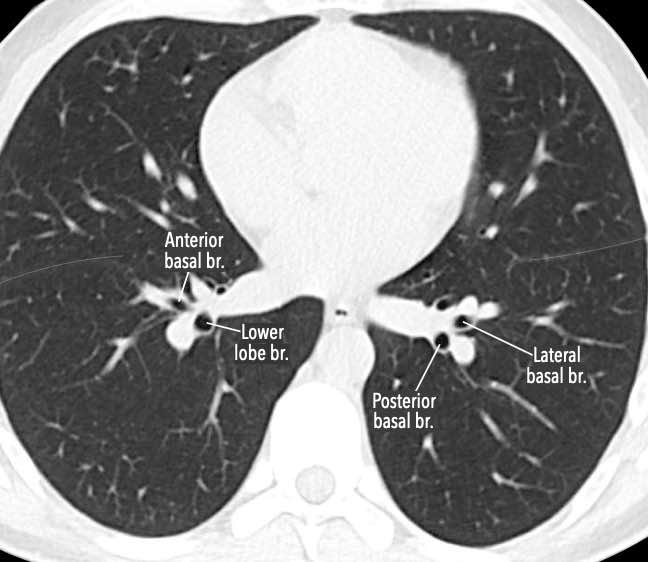

Phế quản trên CT

Cuộn qua các hình ảnh để quan sát khí quản phân chia thành phế quản chính phải và trái, sau đó tiếp tục phân chia thành các phế quản thùy và phế quản phân thùy.